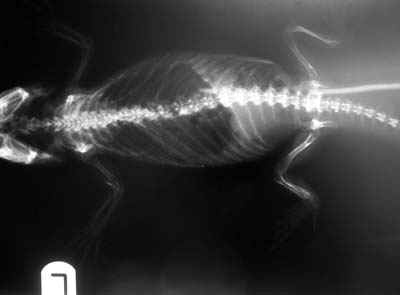

Animals present with a variety of complaints from general lethargy and poor appetite to skeletal deformities and fractures. During examination, the bones can frequently be felt to be soft and plastic, especially the limb and jaw bones. Tortoises may present with very soft shells. Diagnosis is most simply achieved by Xrays.

Bearded dragon with normal skeleton density

Bearded dragon with MBD. Note the distal limb bones are invisible and the pathological fracture